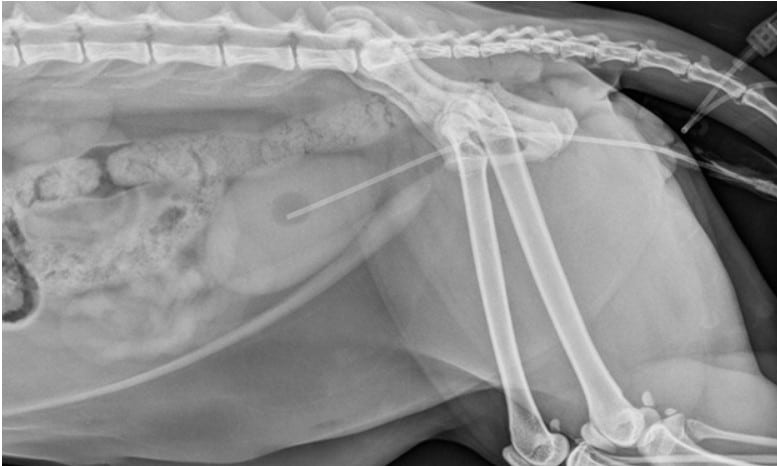

Diagnostics

- Imaging to identify stones/ruptures.